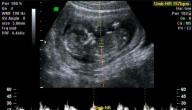

مع الدخول في الشهر الرابع من الحمل وبمرور 16 أسبوعًا تبدأ طاقة الحامل في الاستقرار، وتتغيّر الأمور فيما يخصّ حركة الجنين واحتماليّة الشعور بها، بالتزامن مع ظهور البطن وبروزه واشتهاء أنواع مُحدّدة من الأطعمة أو المشروبات،[١] وفيما يأتي ذكر لأهمّ الأعراض التي تشعر فيها الحامل خلال هذه الفترة:

إذ قد تتمكّن بعض الحوامل من البدء بالشعور بحركة الجنين في الرحم خلال أسابيع الشهر الرابع من الحمل، وقد تتأخّر بعضهنّ حتّى الأسبوع 20 من الحمل قبل أن تُلاحظ أيّ حركة لجنينها، خاصّة إن كان حملها بِكرًا، ويُوصف الشعور حينها بما هو أشبه بالنقرات أو الدّقات الخفيفة، وتزداد شدّتها وعدد مرّات الشعور بها مع التقدّم في الحمل شيئًا فشيئًا.[٣]

التغيرات التي تحدث على الجنين في الشهر الرابع

بمثل ما تتغيّر أعراض الحمل خلال الشهر الرابع من الحمل تتغيّر العديد من الأمور في الجنين أيضًا، وفيما يأتي ذكر لأبرز التغيّرات المتوقّعة خلال هذه الفترة من الحمل:[٥][٦]

• بدء ظهور تعابير الوجه على الجنين، ورغم عدم سيطرته تمامًا عليها إلا إنّها قد تكون ملحوظة خلال الفحوصات وتجعله يبدو عابسًا أو غاضبًا أو مُبتسمًا، كما أنّ عيناه رغم انغلاقهما خلال هذه الفترة إلا أنّهما يُصبحان أكثر حساسيّة للضوء، ما يدفع الجنين لتغيير تعابير وجهه أحيانًا.

• اكتمال نموّ العينان والأذنان تقريبًا، واقترابهما من الشكل النهائيّ المُماثل لشكلهم عند ولادة الجنين.

• يصل طول الجنين لما يُقارب 11.5 سم، وبوزن 110 غرام، وهو ما يُقارب حجم حبّة الأفوكادو أو الليمون.

• يستطيع الجنين تحريك أصابع يديه وقدميه ومفاصل جسمه، وتبدأ أظافر قدميه بالنموّ.

• يُحيط بالجنين ما مقداره 180 مل من السائل الأمنيوسيّ.